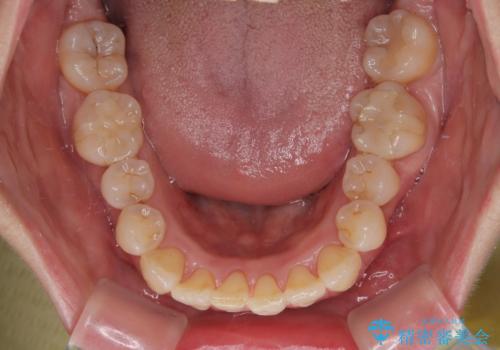

- 上下前歯のデコボコを気にして来院された患者様です。

デコボコは顕著であるものの、口元の突出感は強くないため、非抜歯にて矯正治療を行うこととしました。

元々の叢生と歯肉退縮傾向になる歯肉であったため、ブラックトライアングルが目立つことが想定されました。

治療過程でブラックトライアングル改善のため、IPR(歯と歯の間を削る)を活用しました。